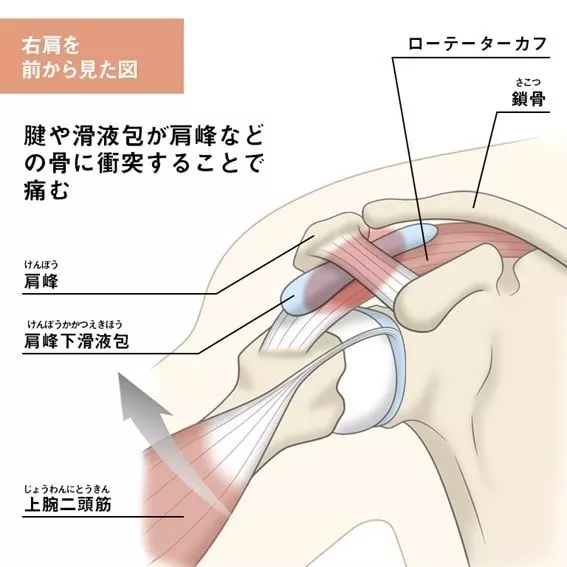

肩を上げるときに痛みや違和感を感じ、動かせなくなる状態を「インピンジメント症候群」と呼びます。

これは、肩を動かす際に上腕骨と肩甲骨の間にある筋肉の腱や滑液包が圧迫されることで発生します。

この圧迫が繰り返されると、滑液包が炎症を起こしたり、出血することがあります。

人が腕を持ち上げると、肩の下のスペースは狭くなりますが、そこには筋肉や靭帯、滑液包が詰まっています。

この狭い空間で筋肉や滑液包が腫れると、骨にぶつかり、肩が痛くなることがあります。